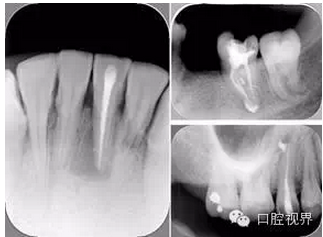

左圖為根管充填術(shù)后 X 線片。圖中可見(jiàn),根管充填較好。右下圖有白色小點(diǎn),為側(cè)方加壓導(dǎo)致糊劑擠出所致,表明根管充填比較致密。

致密、恰到好處的充填可去除干凈根管里感染灶,機(jī)體逐漸恢復(fù)。

多根牙時(shí)候需進(jìn)行偏移投照,正位投照無(wú)法說(shuō)明具體哪根牙根管充填效果。